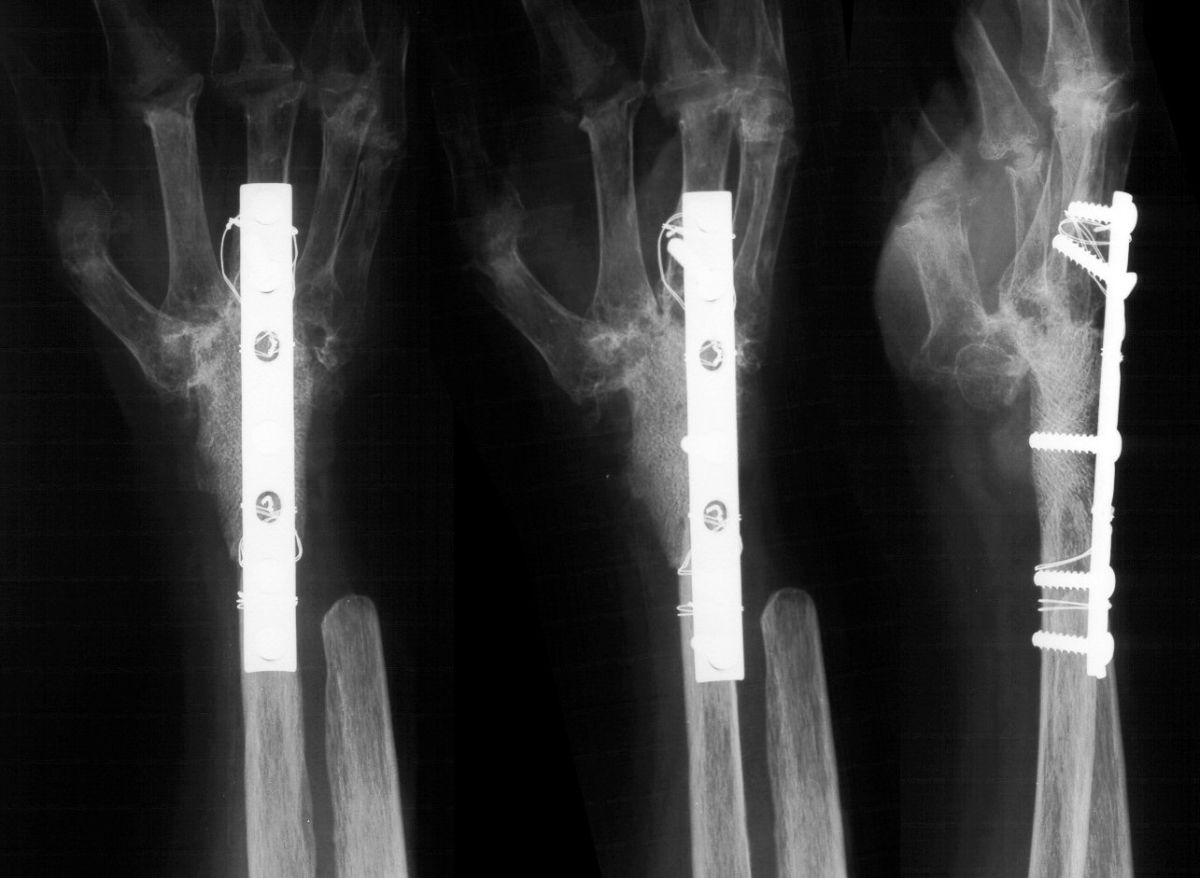

She was treated with wrist arthodesis, using a sculpted fresh frozen femoral head allograft and a cerclage reinforced plate and screw fixation.

Highslide

Late result, showing graft incorporation and remodelling.